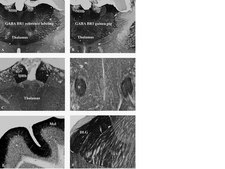

使用经验证可用于WB,IH的抗GABA B受体R1抗体检测GABA B受体R1。

免疫组化:在自由漂浮的小鼠脑组织中的工作稀释度为1:3,000。

目录 # AB2256可识别GABA B受体R1(GABA B R1)